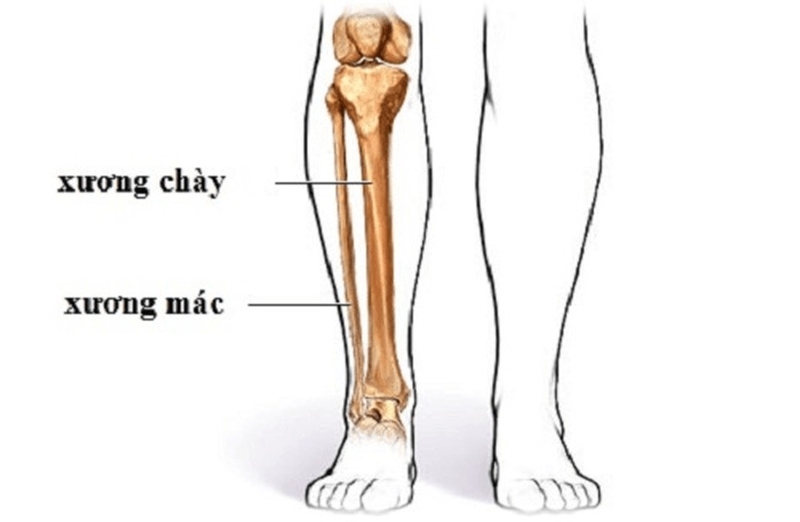

Xương mác là đoạn xương dài nối khớp gối và mắt cá chân, đầu xương dẹt gồm 2 đầu:

Đầu trên: Phần đầu trên của xương mác được gọi là chỏm xương mác. Đây là phần tiếp xúc khớp với xương chày, nằm ở phía trong của chỏm. Chỏm xương mác không tham gia trực tiếp vào việc tạo thành khớp gối, nhưng lại đóng vai trò quan trọng trong việc ổn định khớp và hỗ trợ chức năng của các cơ xung quanh khớp gối.

Đầu dưới: Đầu dưới của xương mác tạo nên mắt cá ngoài, một trong hai mắt cá của bàn chân. Mắt cá ngoài thường thấp hơn mắt cá trong và nằm ở phía bên ngoài của mắt cá trong. Phần mặt trong của đầu dưới xương mác có diện khớp với xương chày, tạo nên sự kết nối ổn định giữa hai xương trong cơ thể.

Thân xương mác: Thân xương mác có hình lăng trụ tam giác, với ba mặt và ba bờ rõ rệt, mỗi phần đều có những đặc điểm riêng.

Cấu tạo đặc biệt của xương mác giúp nó không chỉ ổn định và hỗ trợ trong việc di chuyển, mà còn tham gia vào việc giữ vững thăng bằng cho cơ thể khi đứng hoặc vận động.